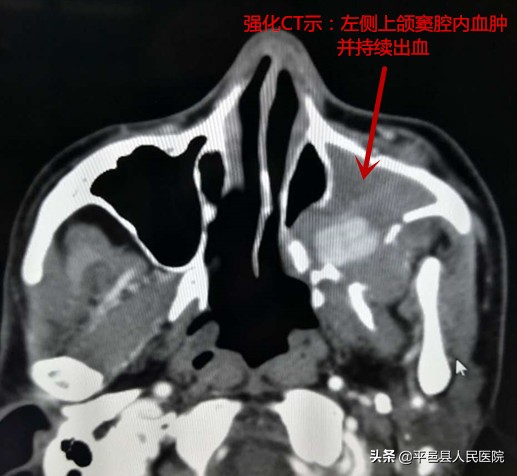

近日平邑县人民医院收治了一位外伤致病情危重的患者,经过多科室综合系统的精心治疗,病情趋于稳定。入院后2周患者突发左侧鼻出血,给予鼻腔填塞等处理,但随后仍不断出血。影像检查提示左侧上颌窦内血肿并持续出血,上颌窦壁多发骨折。